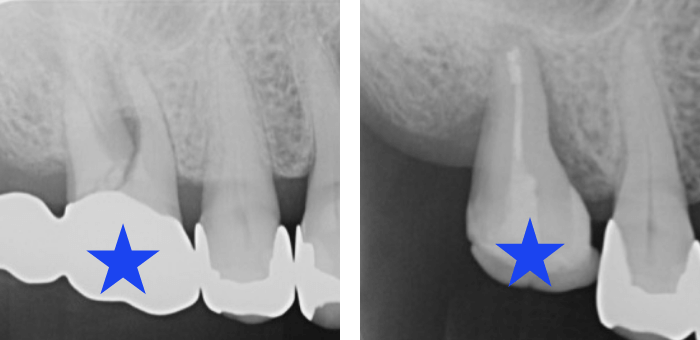

ケース紹介Case Study

レントゲン写真

歯根破折により抜歯となった部位に、親知らずを移植して固定。

6ヶ月後には、骨と歯周組織の再生を確認しました。